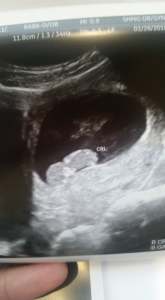

Willow Hope